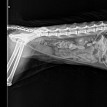

Просьба к специалистам. Расскажите, что не так у кота.

Кот умер, местные норвежские врачи поставили диагноз - отказ почек. Но доверия к ним нет. Два года назад уже пытались усыпить моего кота, признали у него в крови - корона-вирус. И после этого кот прожил ещё полноценно два года.

Кот умер от хронической почечной недостаточности.

Почечные показатели (мочевина, креатинин, фосфор) практическт несовместимы с жизнью.

Действительно, почечные показатели ОЧЕНЬ плохие.